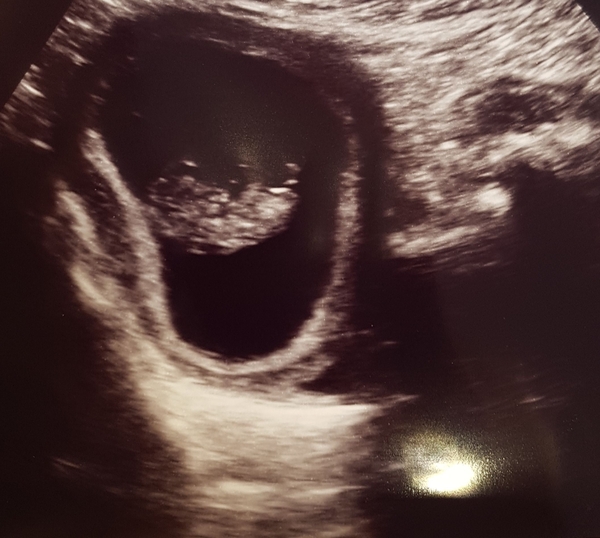

I went for my rescan yesterday.. two weeks ago I was measuring behind at 6+4, when I should've been 7+6.. well it's GOOD news! Baby still has a heartbeat and has, in fact caught up on dates by 3 days. I'm now 9+2 with a wiggly baby who likes to be upside down.. symptoms have eased considerably..

Thanks @balalalala - saw lots of women getting bad news yesterday so I went in expecting the worst, especially when the sonographer was quiet for a while.. but no baby was there wiggling their arms and legs about..

I had brown spotting from 3-5 weeks but an early scan at 6 weeks showed a tiny heartbeat.

I rang the EPU but they can’t do I scan until early next week - so I managed to get a private scan yesterday, it shows a subchorionic haematoma. Amazingly and much to my surprise the baby is happy and measuring a bit bigger than my dates.

The sonography said that the haematoma won’t affect the baby but I could continue to bleed.